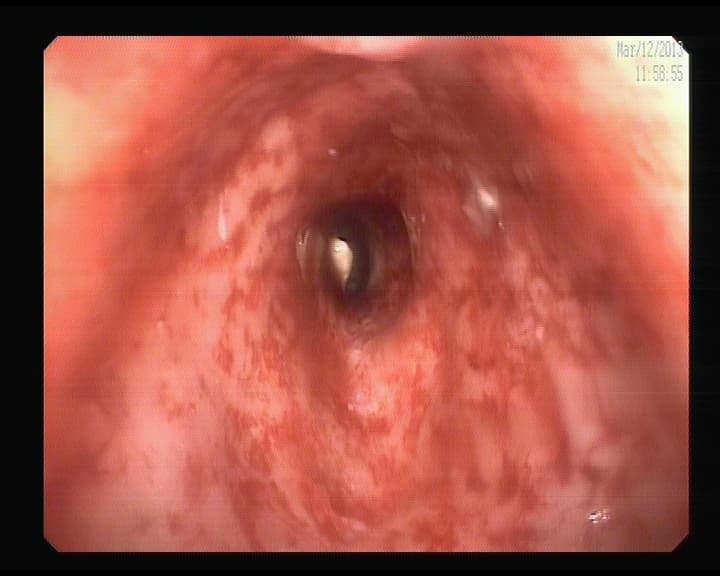

Esofagitis Eosinófilica

El Esófago está infiltrado por células eosinófilas, produciendo resequedad del tejido, y gran aumento de la presión interior, provocando en la persona episodios de atragantamientos- Disfagia transitorias- Síntoma agobiante, atoramiento. Desaparece en minutos, u horas, tranquilizarse, no ingerir nada, y esperar. Si queda el alimento impactado Acudir a un centro hospitalario. No se considera proceso de tipo inmunológico.